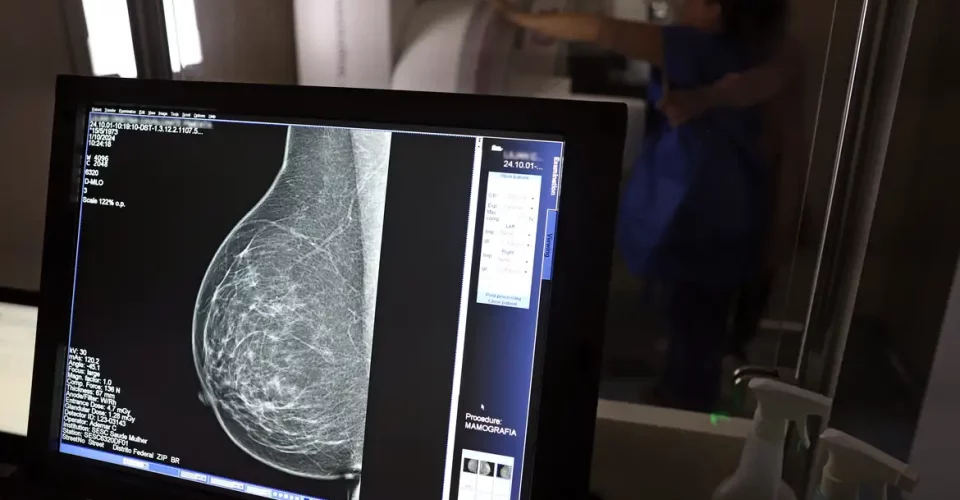

Sesau confirma que mais de 8,6 mil mulheres já realizaram exame de mamografia em 2025

SUS amplia acesso a partir dos 40 anos e solicitação pode ser feita mesmo sem sintomas

O SUS (Sistema Único de Saúde) ampliou o acesso à mamografia para mulheres de 40 a 49 anos, mesmo que não apresentem sintomas da doença. A mudança, anunciada pelo Ministério da Saúde, busca fortalecer o diagnóstico precoce do câncer de mama, que responde por quase um quarto dos casos registrados no país nessa faixa etária.

Com a nova diretriz, o exame poderá ser realizado sob demanda, a partir de decisão conjunta entre a paciente e o profissional de saúde, sem necessidade de histórico familiar ou indicação clínica prévia. O objetivo é facilitar o rastreamento e aumentar as chances de detecção precoce e cura, que podem chegar a 95% quando o tumor é identificado nas fases iniciais.

A ampliação do protocolo também estende o limite de idade para o rastreamento ativo, que passa de 69 para 74 anos, alinhando o Brasil a práticas internacionais de prevenção, como as adotadas na Austrália. Em 2024, o SUS realizou 4 milhões de mamografias de rastreamento e 376,7 mil exames diagnósticos, números que refletem o compromisso com a cobertura nacional e o cuidado integral à saúde da mulher.

Em nota enviada ao Jornal O Estado, a Sesau (Secretaria Municipal de Saúde) informou que “foram realizados, até o momento, 8.605 exames de mamografia em 2025”. O órgão ressaltou que “a recente atualização no protocolo de rastreamento não altera a política adotada pelo município, que já realiza o rastreio do câncer de mama para pacientes dentro desse perfil”.